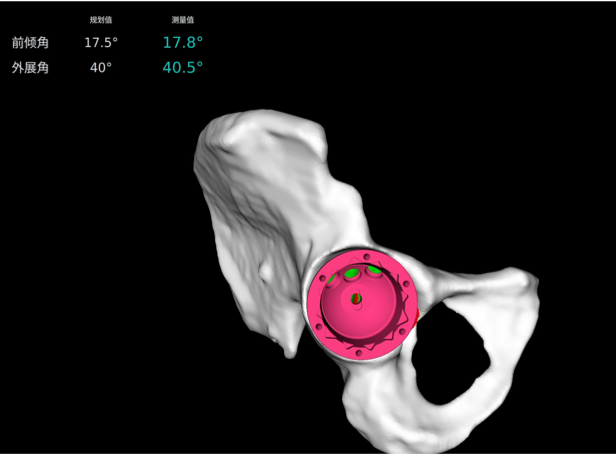

· 實時顯示磨削進度,指示手術(shù)規(guī)劃的磨削區(qū)域,警示過度磨削。

· 精準高效執(zhí)行手術(shù)操作,實時安裝角度顯示,誤差控制在1°以內(nèi)。